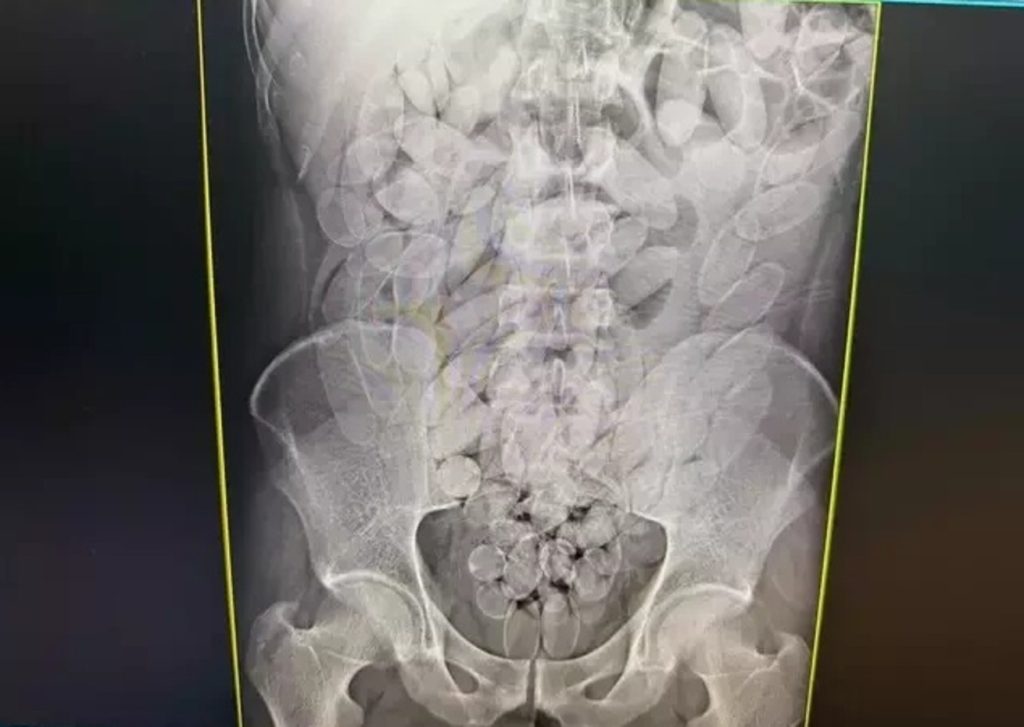

Os raios X mostraram que os oito haviam engolido cápsulas de pasta base de cocaína. A droga foi retirada de forma segura por equipe médica, totalizando 645 cápsulas, publicou o Dourados Informa. Após o procedimento, todos foram encaminhados à PF (Polícia Federal), onde permanecem à disposição da Justiça.